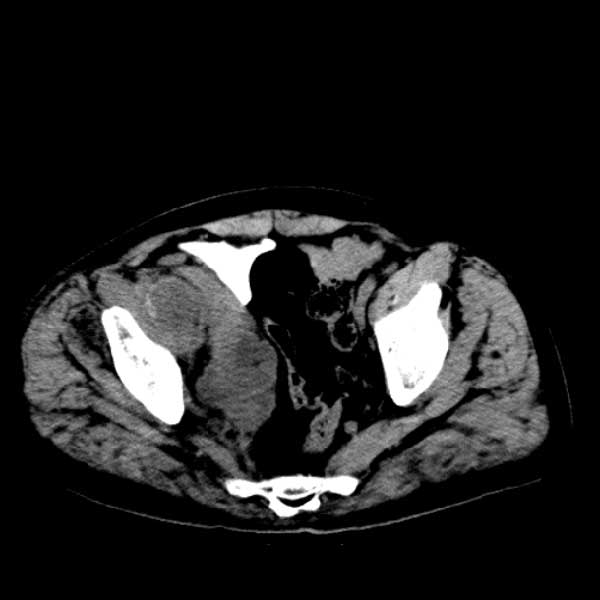

标题: CT13513:男 71 腹部疼痛20余天,近几天高热就诊,骨窗未见异 [打印本页]

标题: CT13513:男 71 腹部疼痛20余天,近几天高热就诊,骨窗未见异

考虑感染性病变可能性大,起源于阑尾?

感染,脓肿形成

考虑为化脓性阑尾炎.脓肿形成.及多肌肉累及.

考虑右侧腰大肌脓肿,向右髂窝、右腹股沟流注。

支持化脓性阑尾炎伴右髂窝脓肿、腰大肌腰方肌脓肿形成。

考虑腹腔及盆腔化脓性炎症,累及右侧髋关节及腹股沟区.

首先考虑化脓性阑尾炎伴腰大肌、腰方肌脓肿,不除外回盲部结核。

回盲部癌待排除。

患者肠镜检查考虑结肠癌,病理证实

患者肠镜检查考虑结肠癌,病理证实。肺部ct可见多发结节,考虑转移